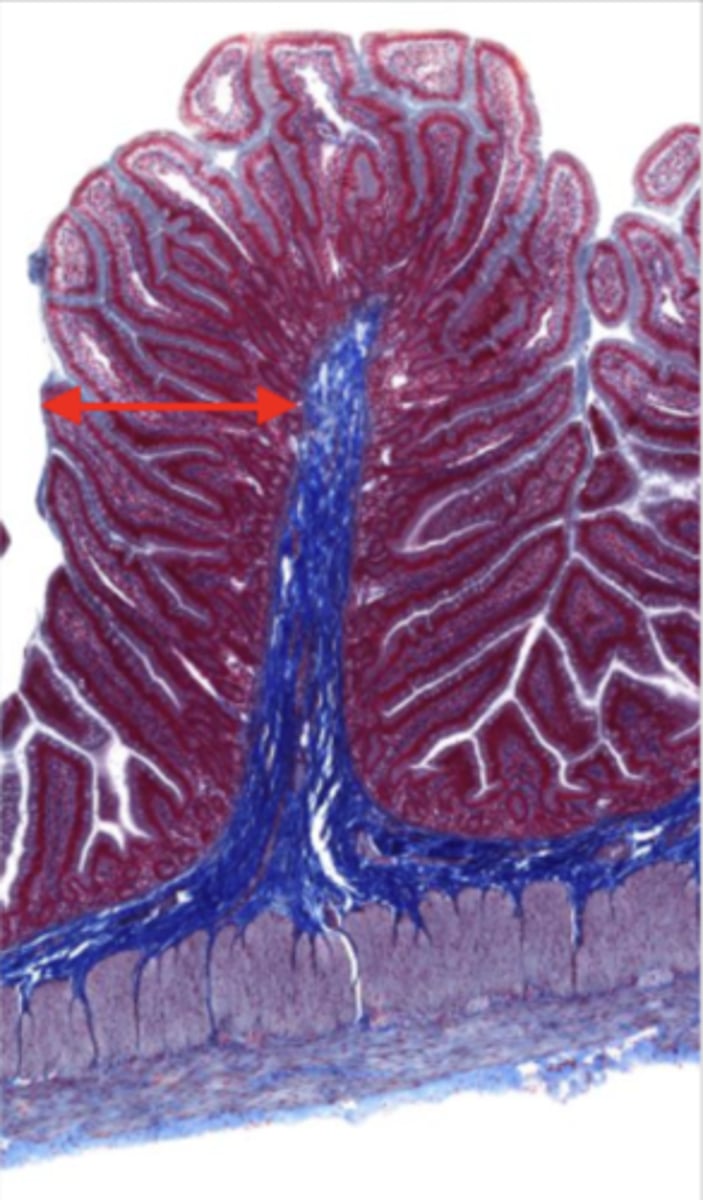

jejunum (histology)

simple columnar epithelium

what kind of epithelium lines the mucosa of the jejunum?

villi (jejunum)

intestinal crypts (jejunum)

lumen (jejunum)

mucosa (jejunum)

mucosal epithelium (jejunum)

lamina propria (jejunum)

muscularis mucosa (jejunum)

submucosa (jejunum)

contains glands and blood supply

muscularis externa (jejunum)

serosa/adventitia (jejunum)